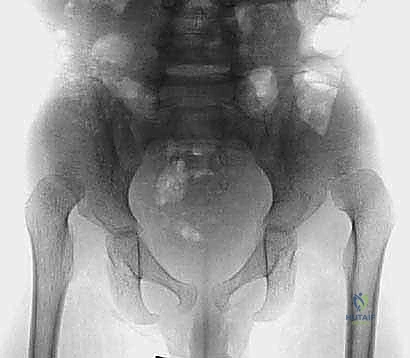

قبل دخول غرفة العمليات، يتم دراسة صور الأشعة السينية والمقطعية (CT Scan) للطفل بدقة، وتحديد زوايا القطع العظمي المطلوبة بالملليمتر.

5. إجراء القطع العظمي (بيمبرتون أو ديجا):

باستخدام أدوات جراحية دقيقة جداً، يتم إجراء القطع العظمي في الحوض وثني سقف الحُق لتغطية رأس الفخذ بالزاوية المثالية التي تم التخطيط لها.